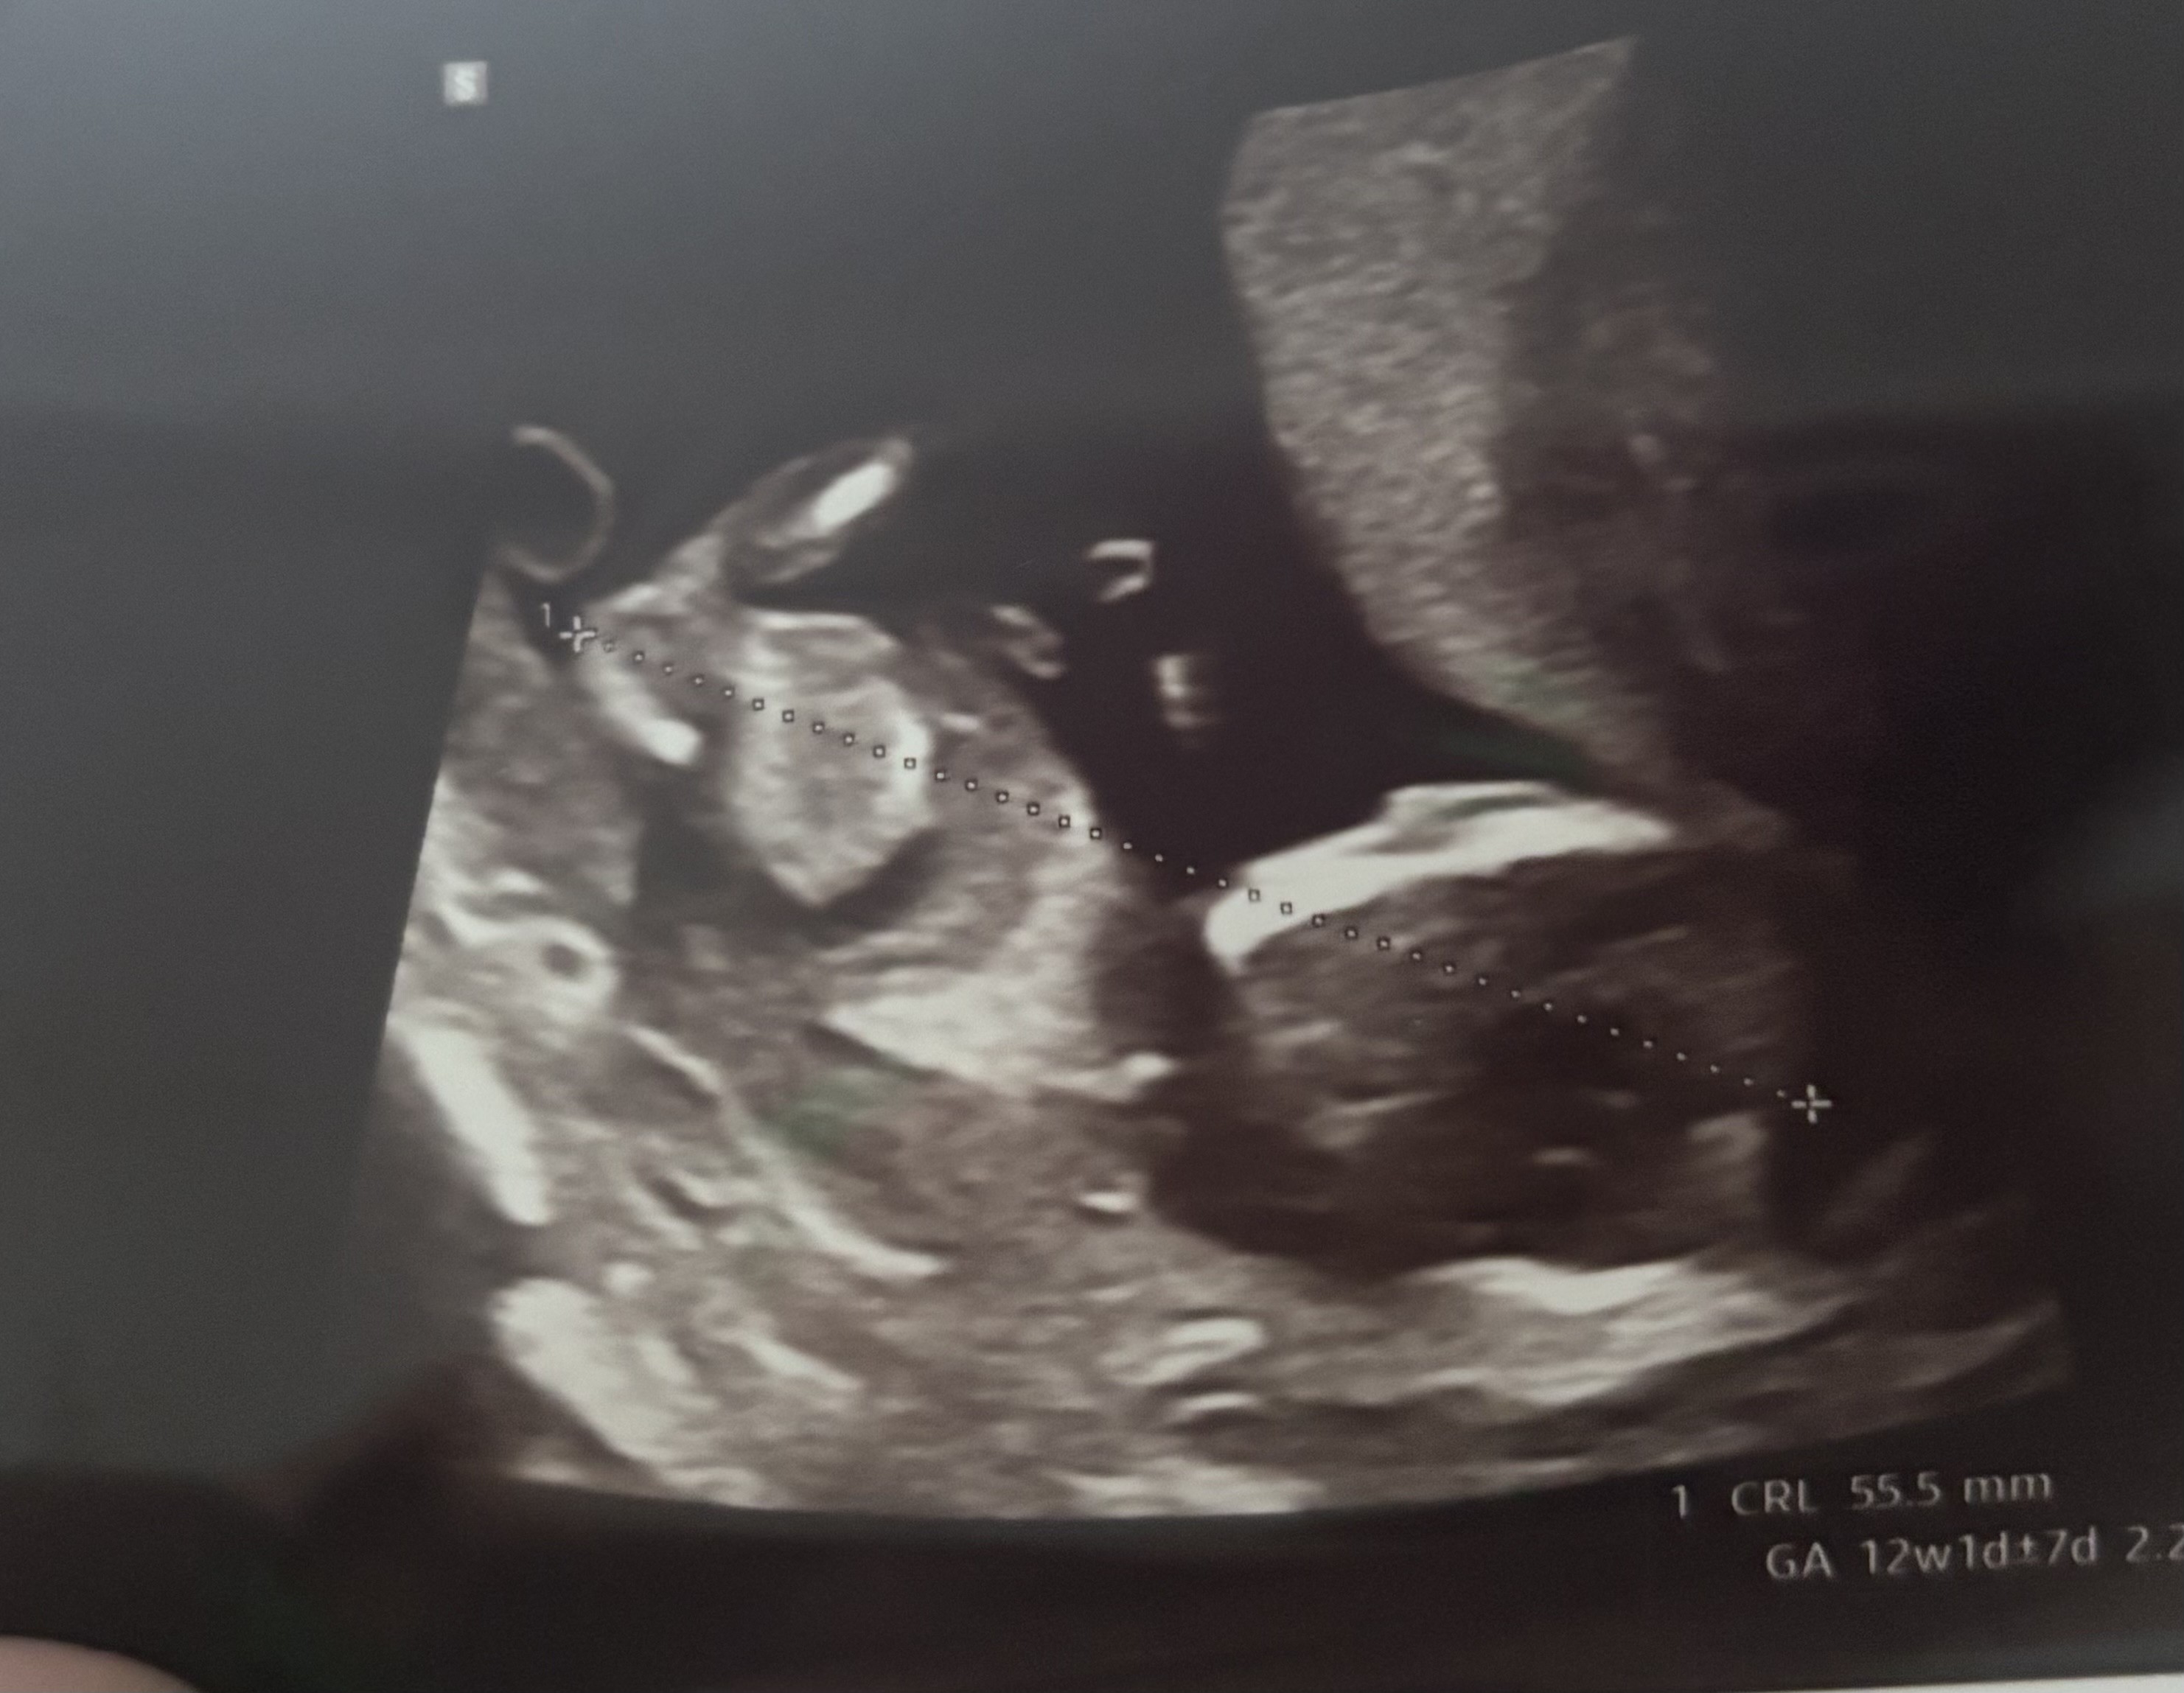

Kochana, spróbuj w chat gpt! Ja tez nie wiedzialam, dla mnie czarna magia, lekarz tylko zasugerował chłopaka, a chat gpt też twierdzi, ze chłopak po wyrostku.Dziewczyny, ja to w tym zielona, a lekarka nie chciała nic sugerować co do płci póki co ale może Wy tu coś widzicie?![]()

Ja też specjalistka nie jestem, ale jeśli mi się dobrze wydaje i dobrze lokalizuje ten wyrostek to chyba dziewczynka?? Bo jest skierowany w dół, nie odstaje do góry.Dziewczyny, ja to w tym zielona, a lekarka nie chciała nic sugerować co do płci póki co ale może Wy tu coś widzicie?![]()

Wrzucałam już do „ajaj” jak ja to mówię ale uznał że nie widać dobrzeKochana, spróbuj w chat gpt! Ja tez nie wiedzialam, dla mnie czarna magia, lekarz tylko zasugerował chłopaka, a chat gpt też twierdzi, ze chłopak po wyrostku.![]()

Ja to tylko tyle że wiem gdzie patrzeć ale nie wiem czego szukaćJa też specjalistka nie jestem, ale jeśli mi się dobrze wydaje i dobrze lokalizuje ten wyrostek to chyba dziewczynka?? Bo jest skierowany w dół, nie odstaje do góry.

Słuchaj wrzuciłam Twoje zdjęcie i wychodzi, ze dziewczynka! Trzeba dobrze sformułować pytanie.Wrzucałam już do „ajaj” jak ja to mówię ale uznał że nie widać dobrzedla mnie teraz chat gpt to w ogóle jak wyrocznia, już Google to nie używam